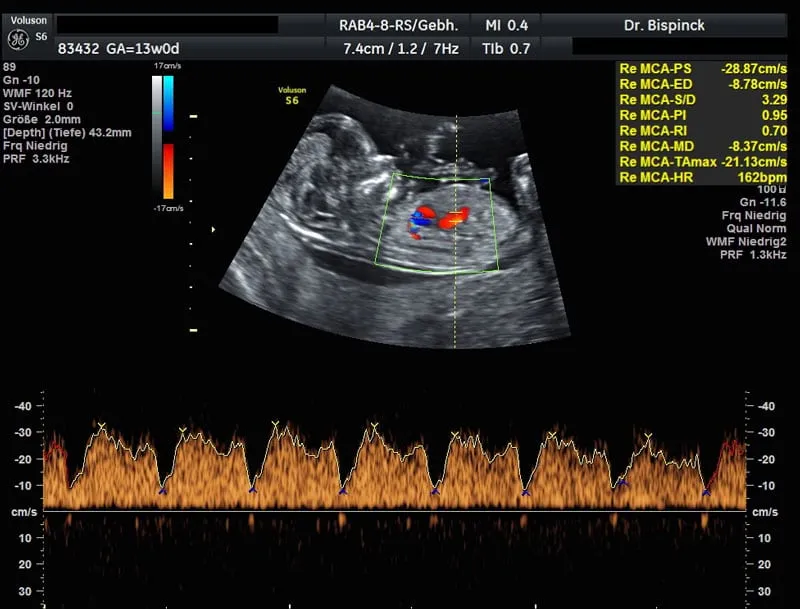

Farbdoppler-Ultraschall